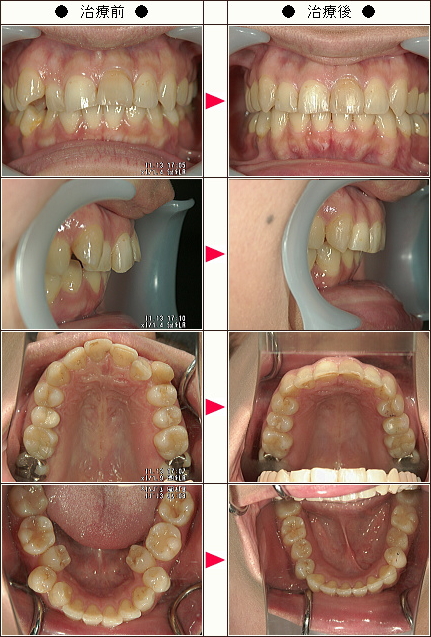

歯のデコボコ矯正症例[A.W.様 21歳 女性]

| 主訴 | 上下の前歯のデコボコと出っ歯 |

| 治療方法 | ワイヤー5か月 マウスピース6か月 |

| 治療期間 | 11カ月 |

| 費用(税込み) | 121万円 |

| 治療等の主なリスク、副作用 | 奥歯を親知らずの方向に動かすために親知らずの抜歯は必須になります |

| 治療詳細 | ワイヤー矯正で奥歯を外側に広げて、親知らずの方向に移動して、できたスペースを利用してマウスピースで前歯を中に入れました |